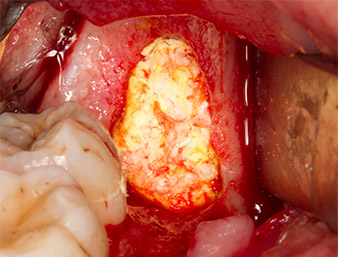

A continuación, el tejido óseo autógeno (figura 13) se incorporó en el alvéolo y en el defecto óseo circundante (figura 14). Un velo de colágeno sirvió de protección para el nervio expuesto y cubrió las virutas óseas hasta el nivel del hueso (figura 15). Se aplicaron puntos de sutura con hilos Vicryl de grosor 4.0, que cerraron los tejidos blandos abiertos (figura 16). Tras la operación, se prescribió un preparado de ibuprofeno (Seractil 400 mg 3x1) y un antibiótico con amoxicilina y ácido clavulánico (Augmentine 1g 2x1).

La parte apical del alvéolo

Imagen 14: La parte apical del alvéolo se cubrió con el tejido autógeno.

velo de colágeno

Imagen 15: El defecto se rellenó con velo de colágeno para proteger el nervio hasta el nivel del hueso. El sangrado inició la fase de cicatrización.